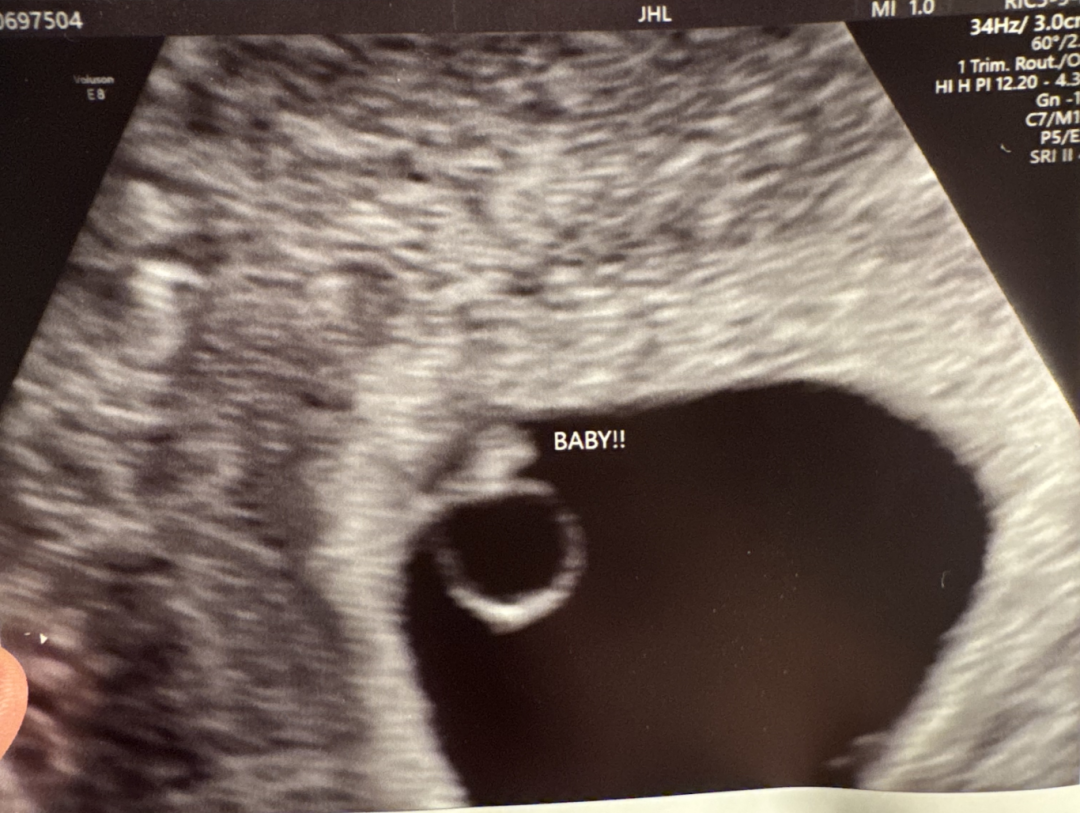

2025年12月,移植后四周B超检查显示:单胎妊娠,孕囊大小与孕周完全相符,可见胎心搏动。